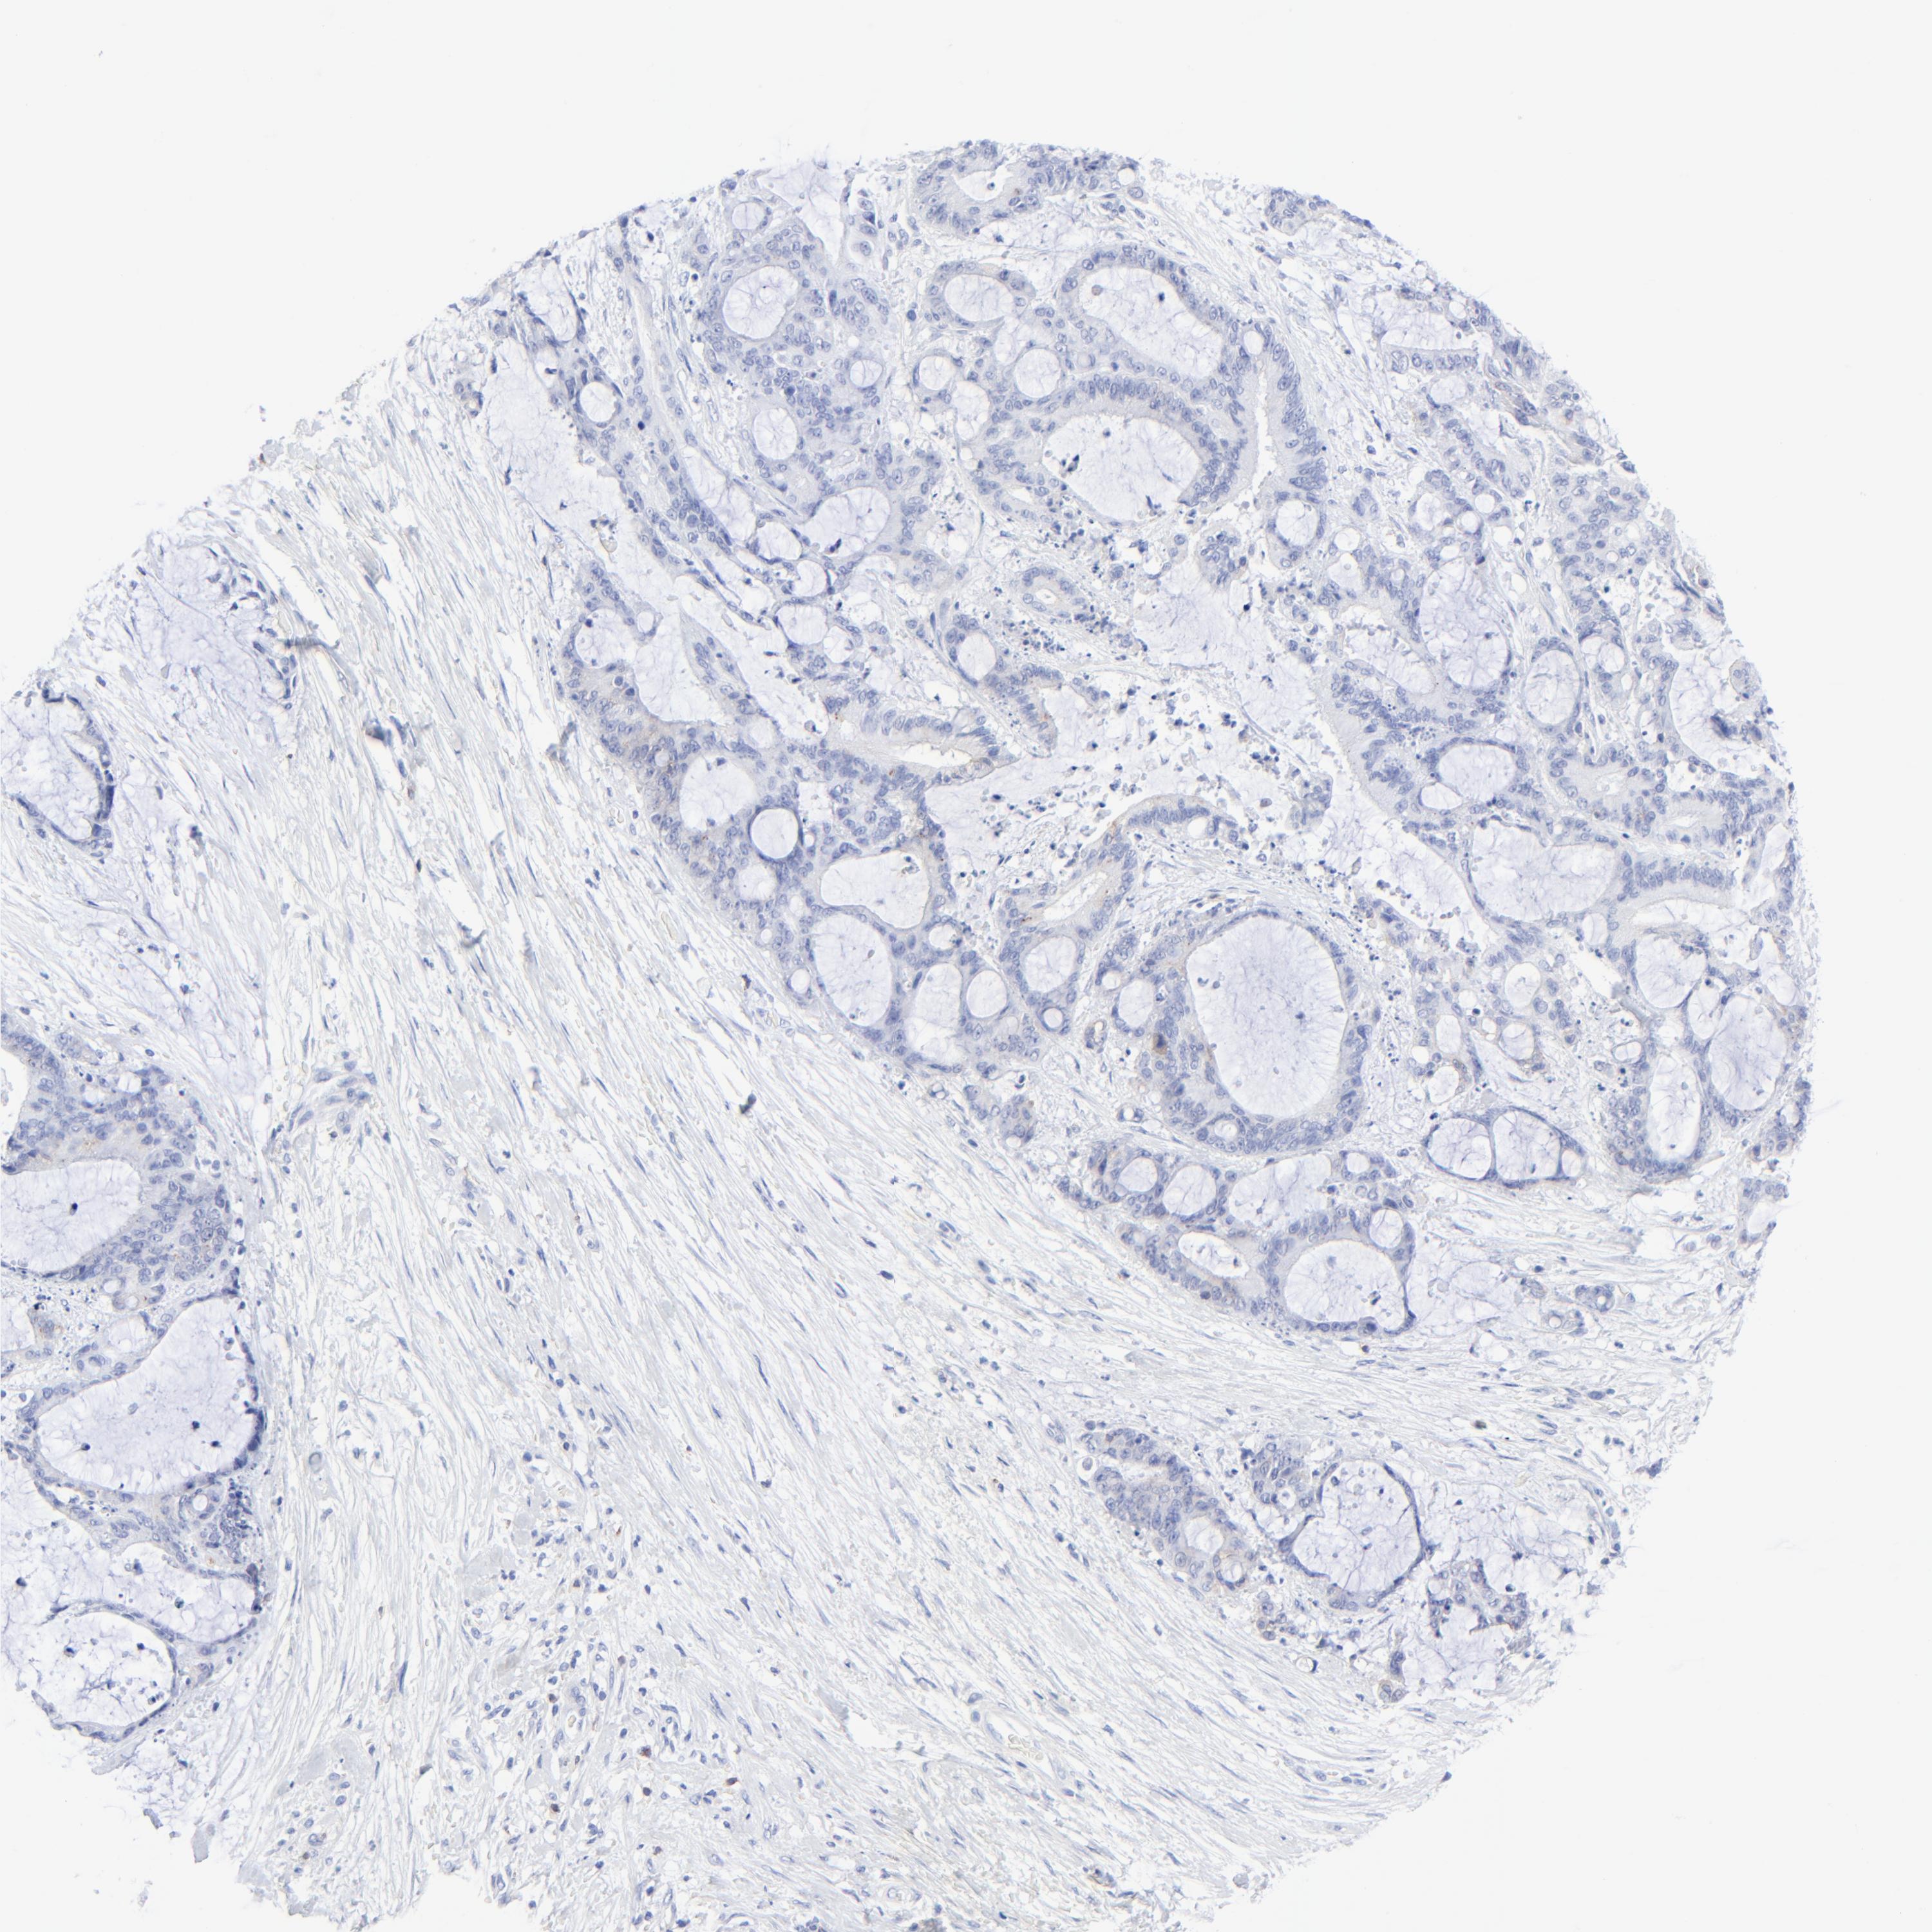

LIVER CANCER - Protein expressioni

A mouse-over function shows sample information and annotation data. Click on an image to view it in a full screen mode. Samples can be filtered based on level of antibody staining by selecting one or several of the following categories: high, medium, low and not detected. The assay and annotation is described here.

Note that samples used for immunohistochemistry by the Human Protein Atlas do not correspond to samples in the TCGA dataset.

Antibody stainingi

Antibody staining in the annotated cell types in the current human tissue is reported as not detected, low, medium, or high, based on conventional immunohistochemistry profiling in selected tissues. This score is based on the combination of the staining intensity and fraction of stained cells.

Each image is clickable and will lead to virtual microscopy that enables deeper exploration of all samples and also displays staining intensity scores, fraction scores and subcellular localization as well as patient and tissue information for each sample.

Antibody HPA003494

Antibody CAB003816

Staining

High

Medium

Low

Not detected

Intensity

Strong

Moderate

Weak

Negative

Quantity

>75%

75%-25%

<25%

None

Location

Nuclear

Cytoplasmic/membranous

Cytoplasmic/membranous,nuclear

Carcinoma, Hepatocellular, NOS

Cholangiocarcinoma